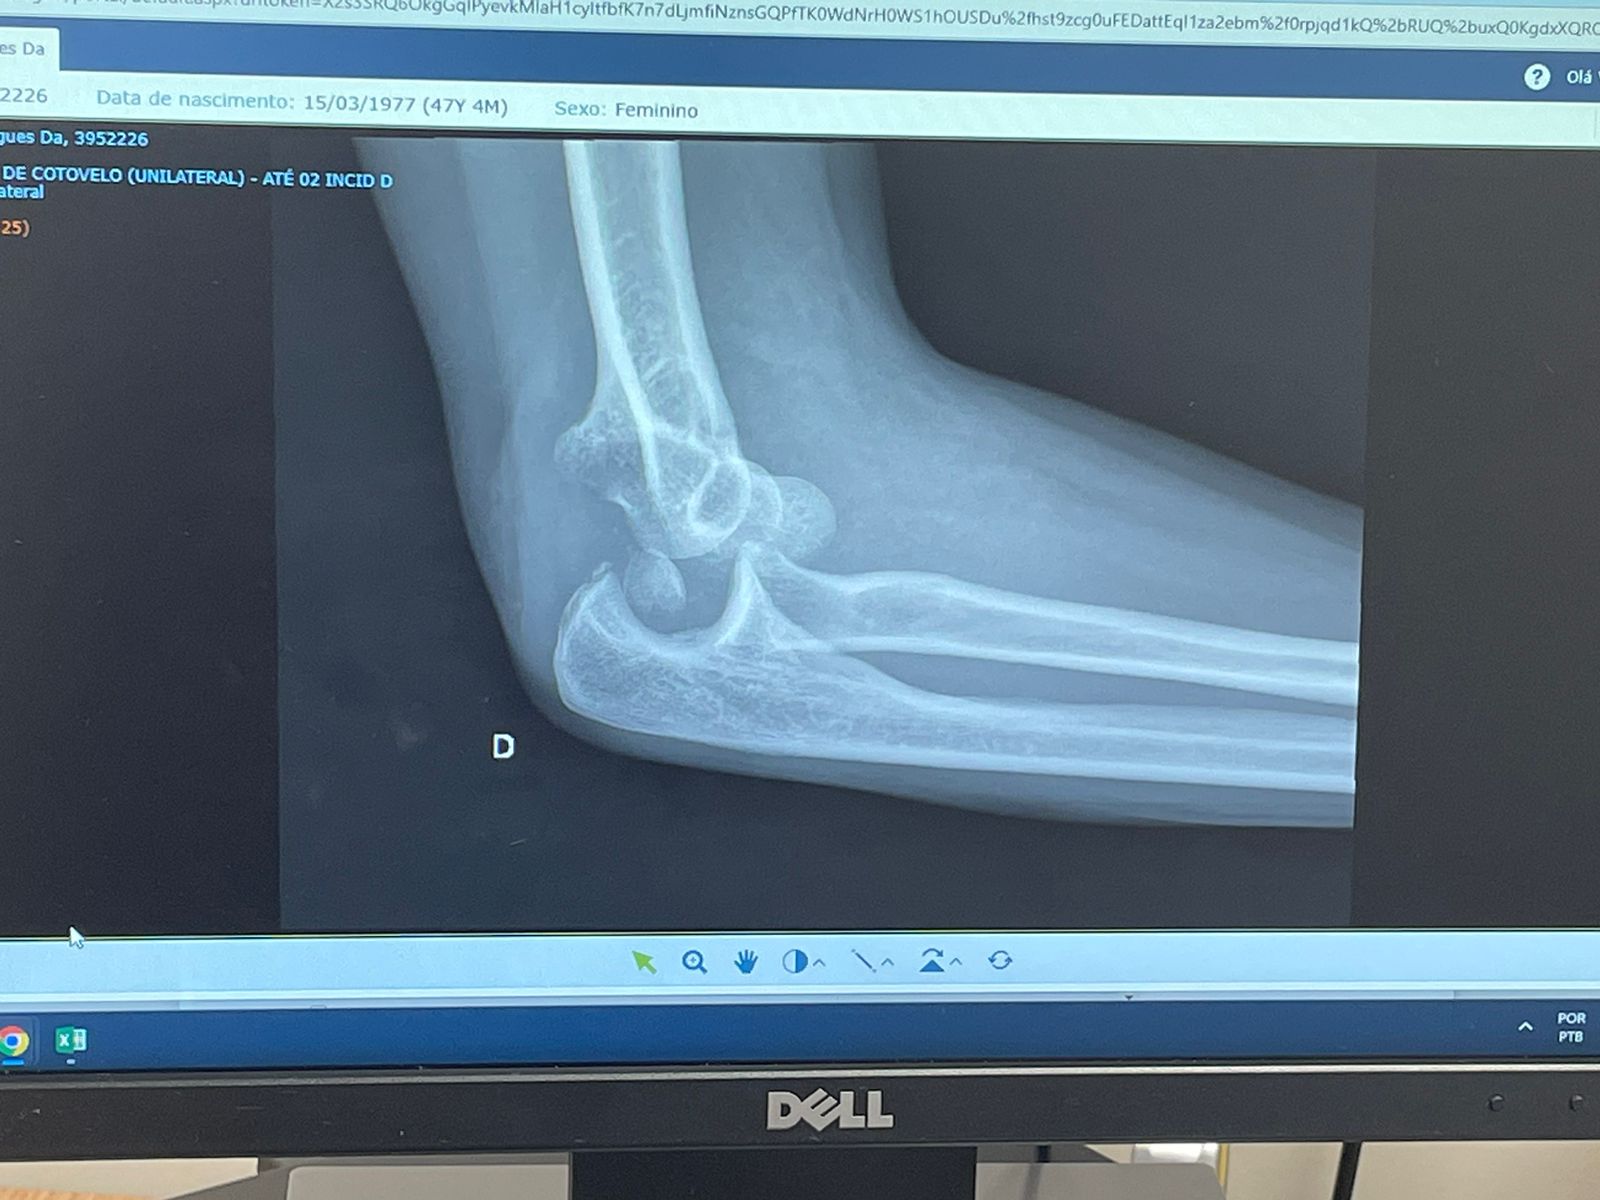

Raio X do braço de Daniela Rodrigues da Silva. Foto: Reprodução

No trajeto, com a bandeira da Palestina visível pela janela, por acaso passaram em frente ao Clube Hebraica. A ação, que não apresentava qualquer ameaça, culminou na violência inaceitável. Com a truculência típica de quem se julga impune, acima da lei, Daniela teve o braço fraturado e no momento se encontra hospitalizada.